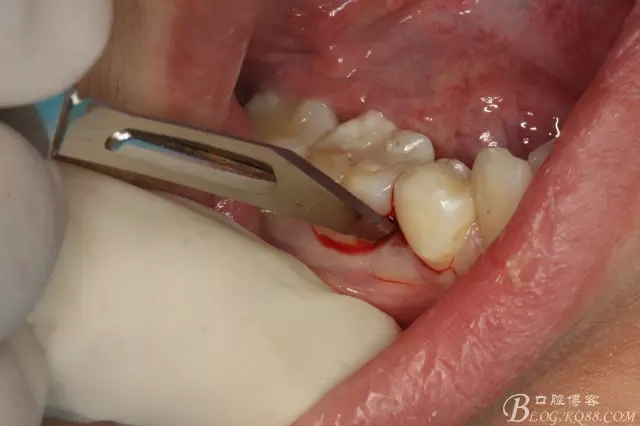

圖5.局部麻醉下、在44近中做垂直小切口,切口不要超過膜齦聯(lián)合。

圖6.齦溝內(nèi)水平切口